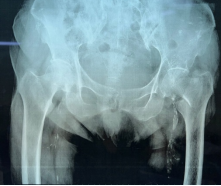

92岁李大爷不慎摔倒后左髋关节疼痛伴左下肢活动受限入住我院骨三病房(关节外科)。在详细查体后,李大爷被诊断为左侧股骨颈骨折。

△术前骨盆平片显示左侧股骨颈骨折